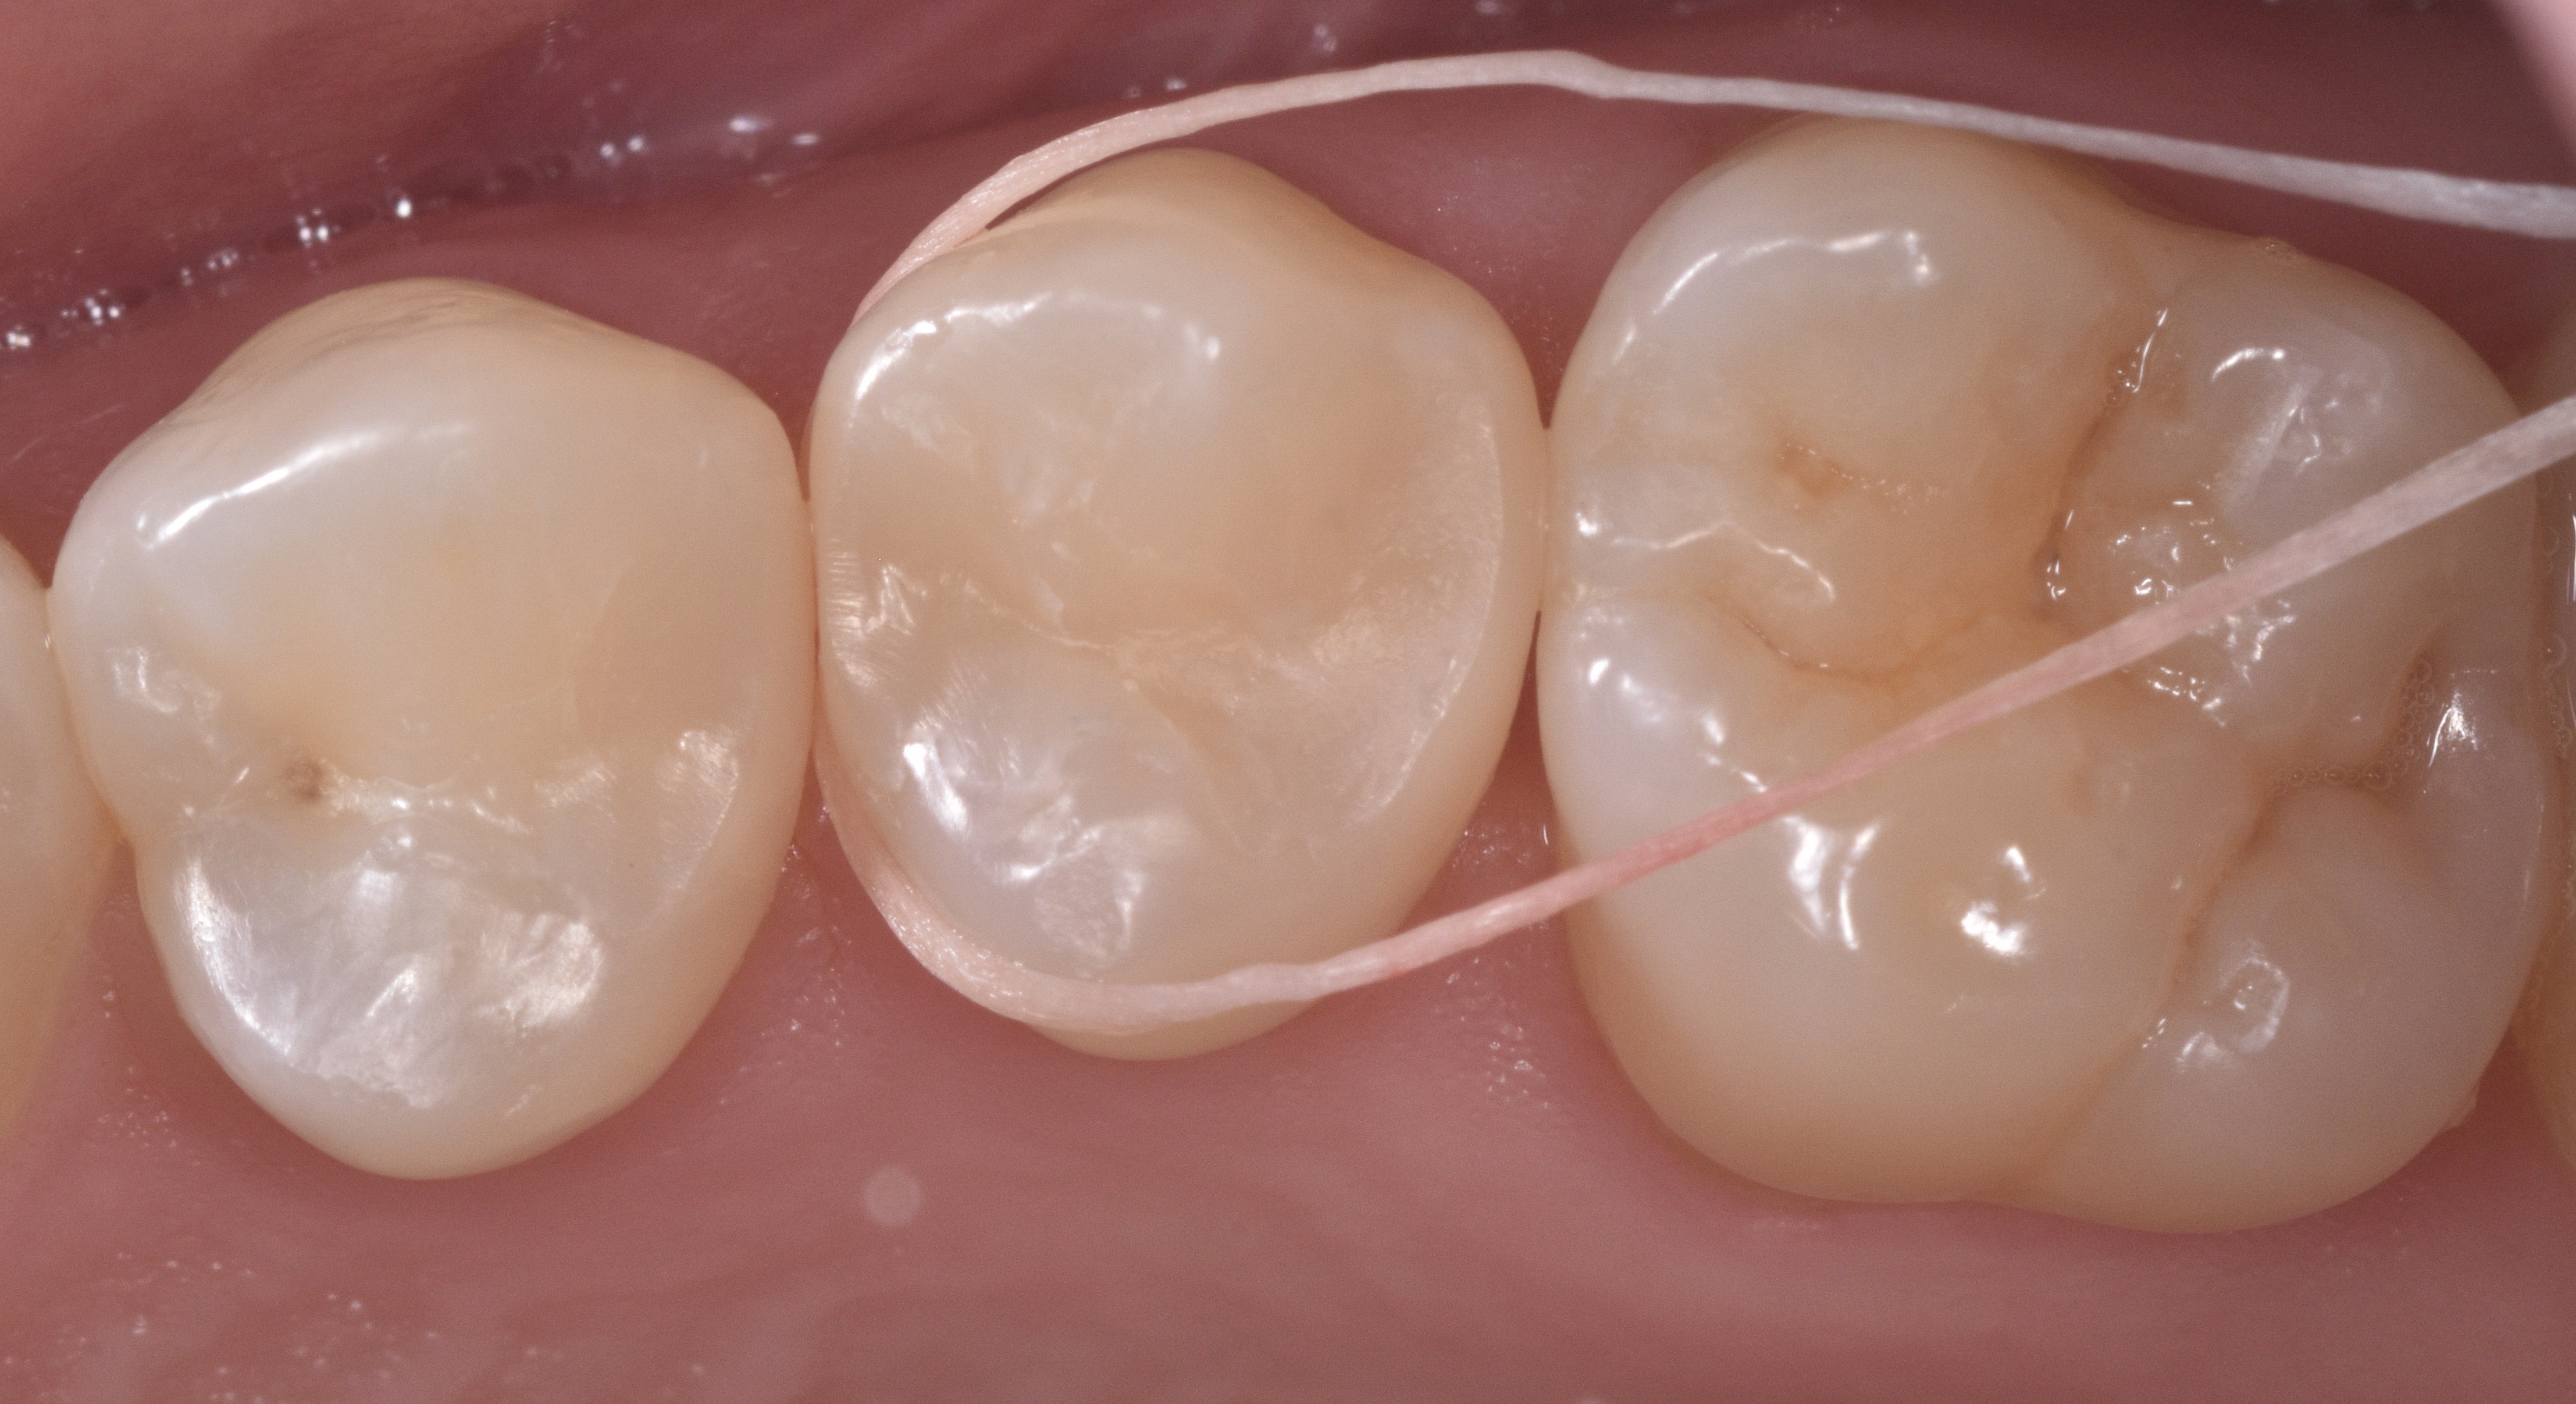

This is followed by removal of the rubber dam, adjusting occlusion, finishing and polishing using a combination of multifluted carbide burs, enhace points and soflex disc (Figure 11). Figures 12 and 13 show the fifteen days post-op follow up and the verification of ideal interproximal contact tightness.

Figure 12

Figure 13

Figure 11Figures 12 & 13